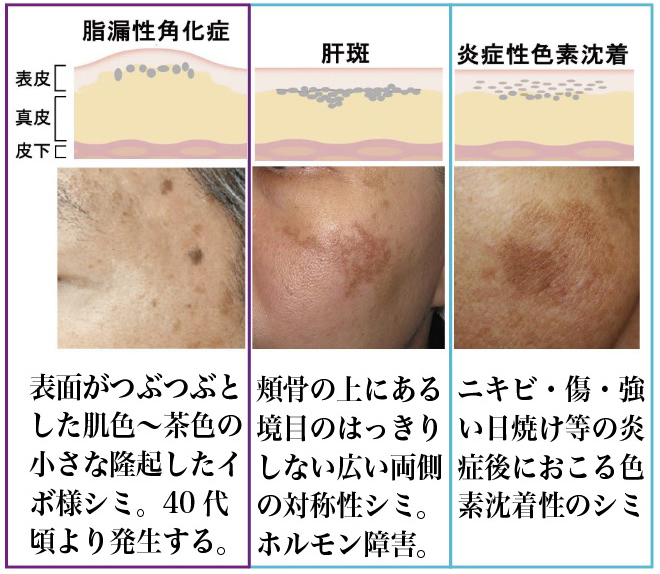

肝斑と色素沈着:違いを理解し、治療方法を学ぶクリーククリニック。

シミだけど、普通のシミでないもの、炎症後の色素沈着徳島の美容クリニック 赤池クリニック。

ニキビ跡の種類は3つあるクレーターだけじゃない!神戸市灘区六甲の美容皮膚科。